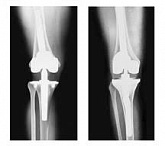

Еndoprosthesis of knee joint

In the late stages of arthrosis of the knee joint, accompanied by a pronounced restriction of the volume of movements, constant intense pain, deformity of the limb, the only way to recover is to replace the affected joint with an artificial joint - arthroplasty.

This method allows you to return the correct form of the limb, the full volume of movements in the joint, relieve the constant pain and crunch during movements and, as a result, significantly improve the patient's quality of life.

Below are presented X-ray photographs and photographs, illustrating the amount of motion in the affected joint before and after surgery.